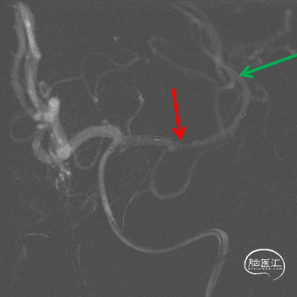

DSA

1、急性脑梗死。2、左侧大脑中动脉M1段闭塞。

ICAS合并血栓?

夹层合并血栓?

栓塞?

微导丝前行有阻力,调整后通过

微导管通过后回撤

首过效应(+)

心玮 4-40取栓支架释放后,支架释放效应(+)

管壁毛糙,泵替罗非班观察15分钟(60Kg,静脉推注7ml后7ml/h微泵维持)。

15分钟后“打回原形”

1、原位血栓?→替罗非班已泵

2、ICAS闭塞?

3、夹层含壁间血肿成分再次闭塞?